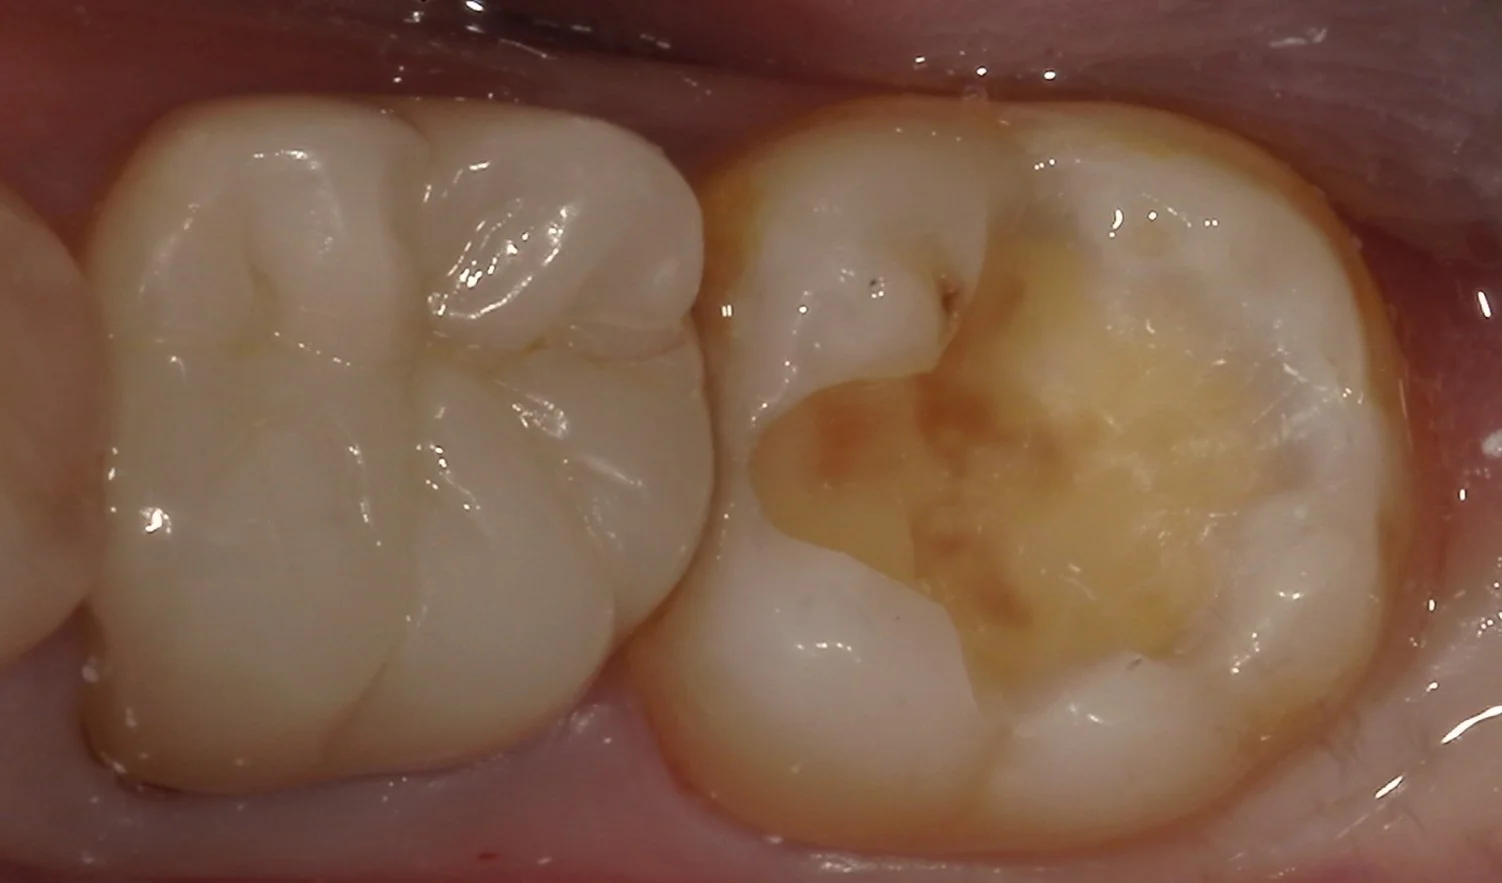

虫歯を取りきるとこんな感じでした。

非常に大きかったので、所々着色が残ってしまっていますが、別に虫歯というわけではありません。

健康な層がしっかりと露出させることが出来たので、そのまま詰めていきます。